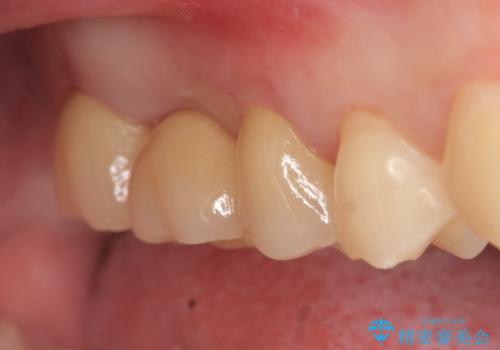

その後歯茎や骨の回復を待ち、オールセラミッククラウンのブリッジによる補綴を行いました。

今回用いたオールセラミッククラウンはジルコニアフレームという白い素材の上にセラミックを盛っているため、審美性が非常に高いのが特徴です。

また、ジルコニアは人工ダイヤモンドの材料にも使われているほど高い強度を持っており、そのためオールセラミッククラウンは審美性だけでなく、奥歯やブリッジの補綴も可能とするクラウンです。